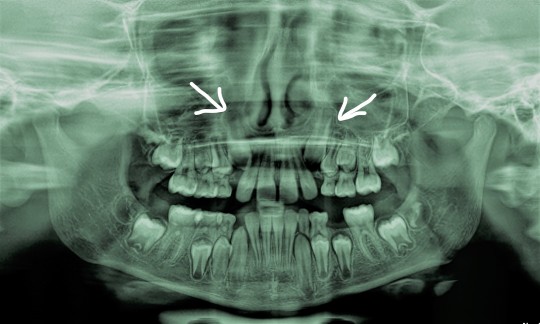

There is quite common problem with canines. We can see teenagers with unerupted canines. It happens in case the total width of the teeth exceeds the available width of the arch for the teeth to erupt in to.

+

Fig. 5. X-ray photo of unerupted canines